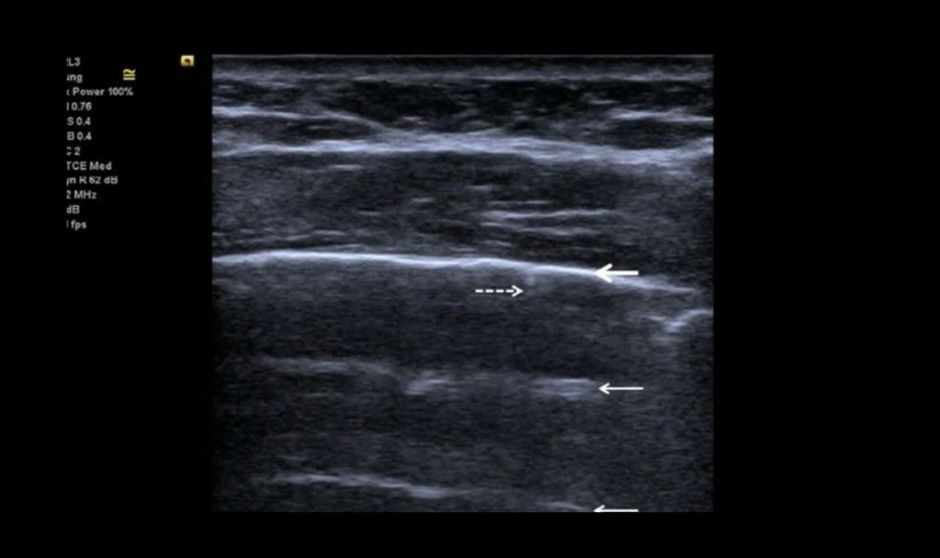

Seguimiento de un paciente de UCI con neumonía Covid-19.

“Debido al desarrollo continuo de su estado clínico, los pacientes ingresados por Covid grave necesitan con frecuencia imágenes de tórax. La ecografía torácica puede hacer una contribución sustancial, ya que permite el examen directo de cabecera del pulmón y el espacio pleural. Estos pacientes muestran neumonía intersticial bilateral difusa, con lesiones irregulares y parcheadas distribuidas principalmente en la periferia del pulmón”, explican los autores en un artículo publicado en SpringerOpen.

En este contexto, los expertos destacan que la ecografía pulmonar sirve para evaluar rápidamente la gravedad de la neumonía por SARS-CoV-2, ya que rastrea la evolución de la enfermedad durante el seguimiento y monitorea las maniobras de reclutamiento pulmonar. Además, argumentan que la ecografía puede rastrear la respuesta a la ventilación en decúbito prono y el control de la terapia de membrana extracorpórea.